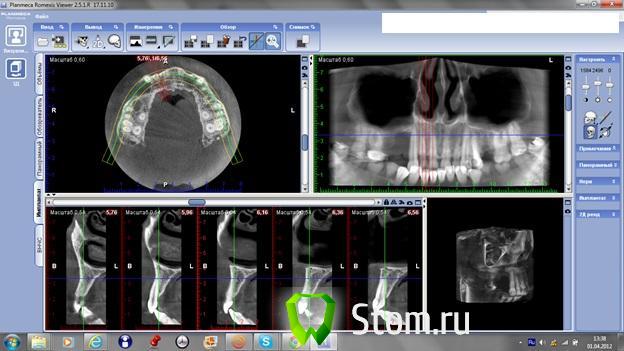

samsonov Опубликовано 4 апреля, 2012 Поделиться Опубликовано 4 апреля, 2012 Здравия желаю всем.Что думаете о возможностях внутриротового забора кости для пластики в районе14-15?Или всё таки - внеротовой вариант надёжнее? Ссылка на комментарий

Sahan Опубликовано 4 апреля, 2012 Поделиться Опубликовано 4 апреля, 2012 Здравия желаю всем.Что думаете о возможностях внутриротового забора кости для пластики в районе14-15?Или всё таки - внеротовой вариант надёжнее?Не совсем видно , что там с 13? Оголена только дистальная поверхность корня или еще где то есть оголения? Что до пластики, то здесь внутриротовой кости будет достаточно. Я бы пластику провел с использованием титановой мембраны цитопласт. Ссылка на комментарий

samsonov Опубликовано 4 апреля, 2012 Автор Поделиться Опубликовано 4 апреля, 2012 Не совсем видно , что там с 13? Оголена только дистальная поверхность корня или еще где то есть оголения? Что до пластики, то здесь внутриротовой кости будет достаточно. Я бы пластику провел с использованием титановой мембраны цитопласт.дистальная поверхность почти до апекса,зуб ещё жив .Считаете,с подбородка хватит? Ссылка на комментарий

Sahan Опубликовано 4 апреля, 2012 Поделиться Опубликовано 4 апреля, 2012 (изменено) Я бы тоже предпочел бы ветвь. Если вокруг 13 везде есть кость кроме дистальной поверхности , есть шанс спасти. Как нибудь выложу КТ до и после. Изменено 4 апреля, 2012 пользователем Sahan Ссылка на комментарий

doca Опубликовано 5 апреля, 2012 Поделиться Опубликовано 5 апреля, 2012 Здравия желаю всем.Что думаете о возможностях внутриротового забора кости для пластики в районе14-15?Или всё таки - внеротовой вариант надёжнее?Если будете делать пластику,то 13 уходит ,не прирастет костьк нему.после этого 3д реконструкцию по горизонтали и вертикали,потом с десной работа.Если не хватит кости с ветви,добирайте с подбородка. Ссылка на комментарий